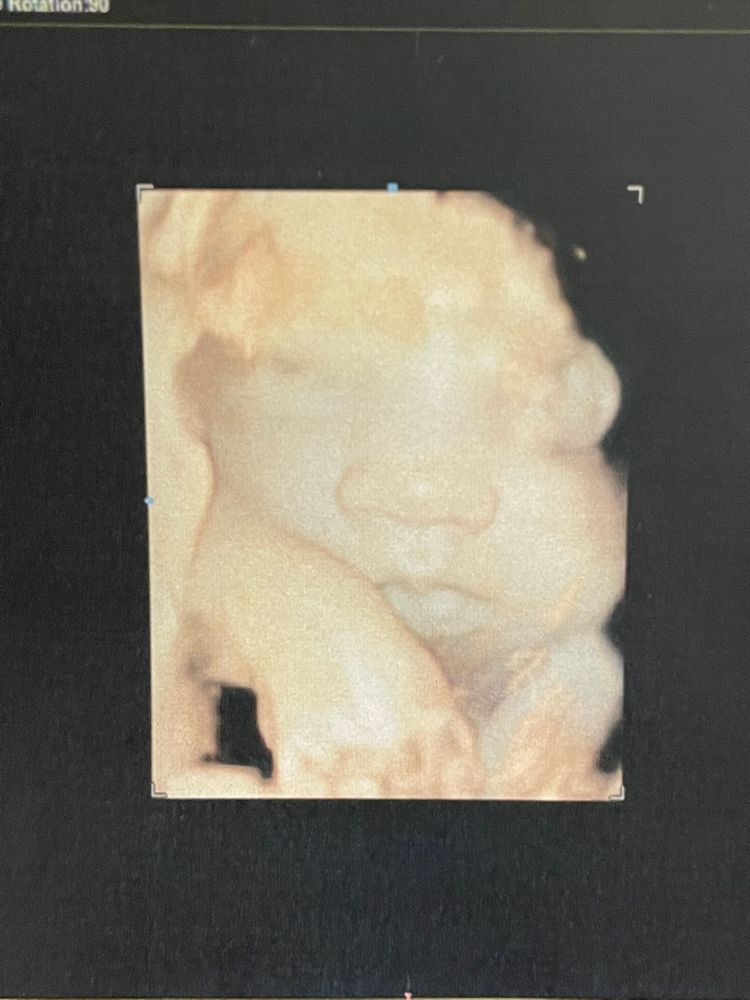

Побежала записываться к Тё С.А. Увидела снова свою куколку ❤️ 32.5 срок, по узи на 33.0. Вес 2300, сказал к родам будет 3600 примерно (а у меня все дети 3540-3610). Воды в норме, по верхней границе, но норма. Ну и никакой макроглоссии. Рубец 3мм, без изменений. Всё, что он смог найти за 50 минут - это возможно киста слюнных желёз под язычком. Но она была очень активная и не дала это опровергнуть.

Ждём встречи 🙏🏻😻🥰